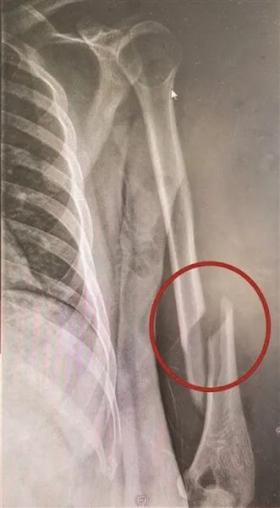

掰手腕掰断的,大部分是肱骨,这与肱骨的结构与受力方式有关系。

首先,我们的肱骨本身很长,到了靠近肘关节的部分,厚度逐渐变薄,形状也逐渐变窄。

如果啃过羊棒骨的话你就会知道,肘关节上方的位置是最为薄弱的,这个地方医学上叫肱骨踝。

因为人类活动方式等原因,肱骨踝承受牵引力的能力比较强,所以,在我们平时拎东西、搬东西时,因为是顺向受力,肱骨踝 so easy。

但在人类掰手腕的时候,因为是扭动的发力,所以肱骨踝承受的是一种剪切力。

而无论是肱骨还是肱骨踝,它们承受剪切力的能力都很弱,如果再加上姿势不对,或者骨密度低等原因,就很容易扭断胳膊。